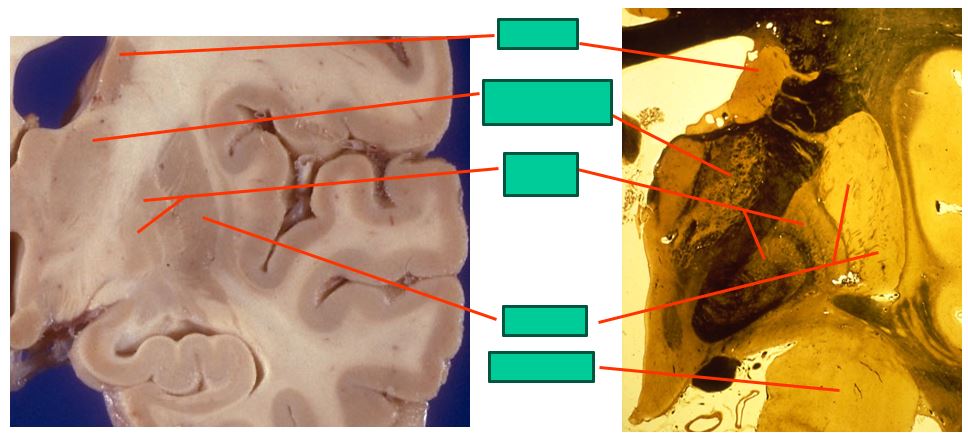

the caudal level of the basal ganglia look like this

includes:

caudate

ventrolateral thalamus

ventroanterior thalamus

globus pallidus

putamen

subthalamic nucleus